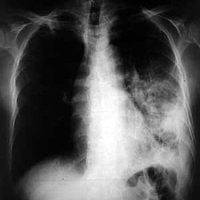

Doit-on craindre un retour de la tuberculose en France ?

03/05/2010Trois cas de tuberculose déclarés dans un collège de Seine-Saint-Denis et un dépistage massif est organisé. Accalmie de courte durée après l’épisode de la grippe A… Un vent de panique pointe son nez, les médias parlent d’une recrudescence de la maladie. Paranoïa ou inquiétude légitime ? Le point avec le Dr Philippe Fraisse*, coordonnateur du groupe "tuberculose" de la Société de Pneumologie de Langue Française et enseignant à l’IFSI de Strasbourg.